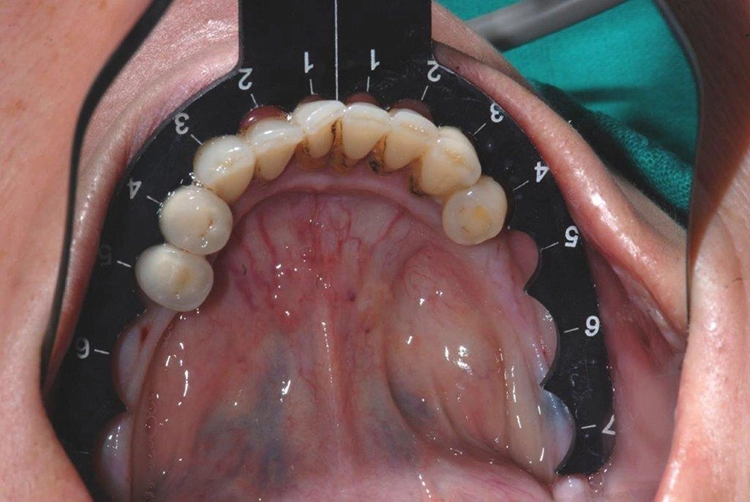

Die zweite, „prothetische“ Navigationshilfe sind die CHAMPIONS Implantat Guides (einer für Oberkiefer, der andere für den Unterkiefer). Sie sind sehr preiswert und als Schablone in der GOZ abrechenbar. Sie sind immer wieder verwend- und sterilisierbar und durch Verformung an jeden Kiefer anpassbar (Abb. 15 und 16).